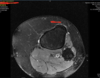

Superficial fissuring of the lateral patellar facet cartilage, normal patellar ratios, TTTG 26mm

Isolated 2cm2 grade 4 chondral defect of the lateral patella facet with a normal trochlea.